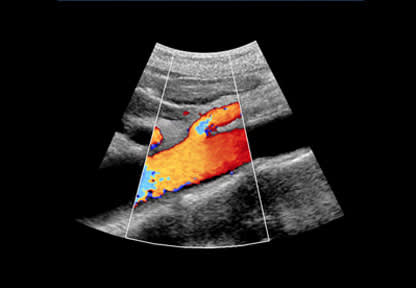

Screening involves a simple ultrasound scan of your stomach (abdomen), which takes about 10-15 minutes.

The screening test for AAA is a simple, pain-free ultrasound scan of the abdomen that usually takes about 10-15 minutes.

The screening technician will ask you to lift up your shirt and then run a small ultrasound scanner on your abdomen, which will allow the thickness of your abdominal aorta to be measured on a monitor.